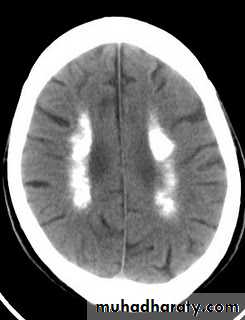

Clinical features of hypocalcaemia

Because of associated hyperphosphataemia, patients with hypoparathyroidism may develop calcification of the basal ganglia, grand mal seizure, psychosis and cataract.